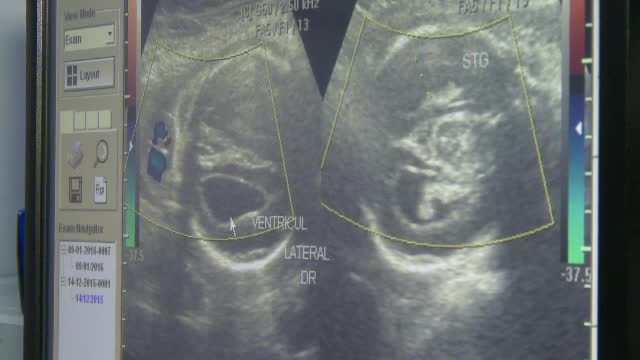

Femeia care a aflat ca va naste un bebelus cu malformatii a depus plangere la Colegiul Medicilor. Pe cine dau vina parintii

Femeia din Constanta, insarcinata in 9 luni, care a aflat abia acum ca va naste un copil cu grave malformatii, a depus ...

O sarcina in care copilul "nu are cerul gurii si are malformatii grave", catalogata drept "normala". Acuzatiile unei gravide

Suspiciuni de malpraxis planeaza asupra sefei unei clinici medicale private din Bucuresti, o doctorita ginecolog iesita ...